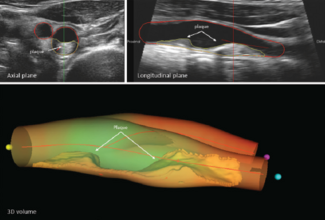

The progression of atherosclerosis in people who have no symptoms of it is independently associated with the risk of dying from any cause, according to a new study led by researchers from Mount Sinai Fuster Heart Hospital, published in the...